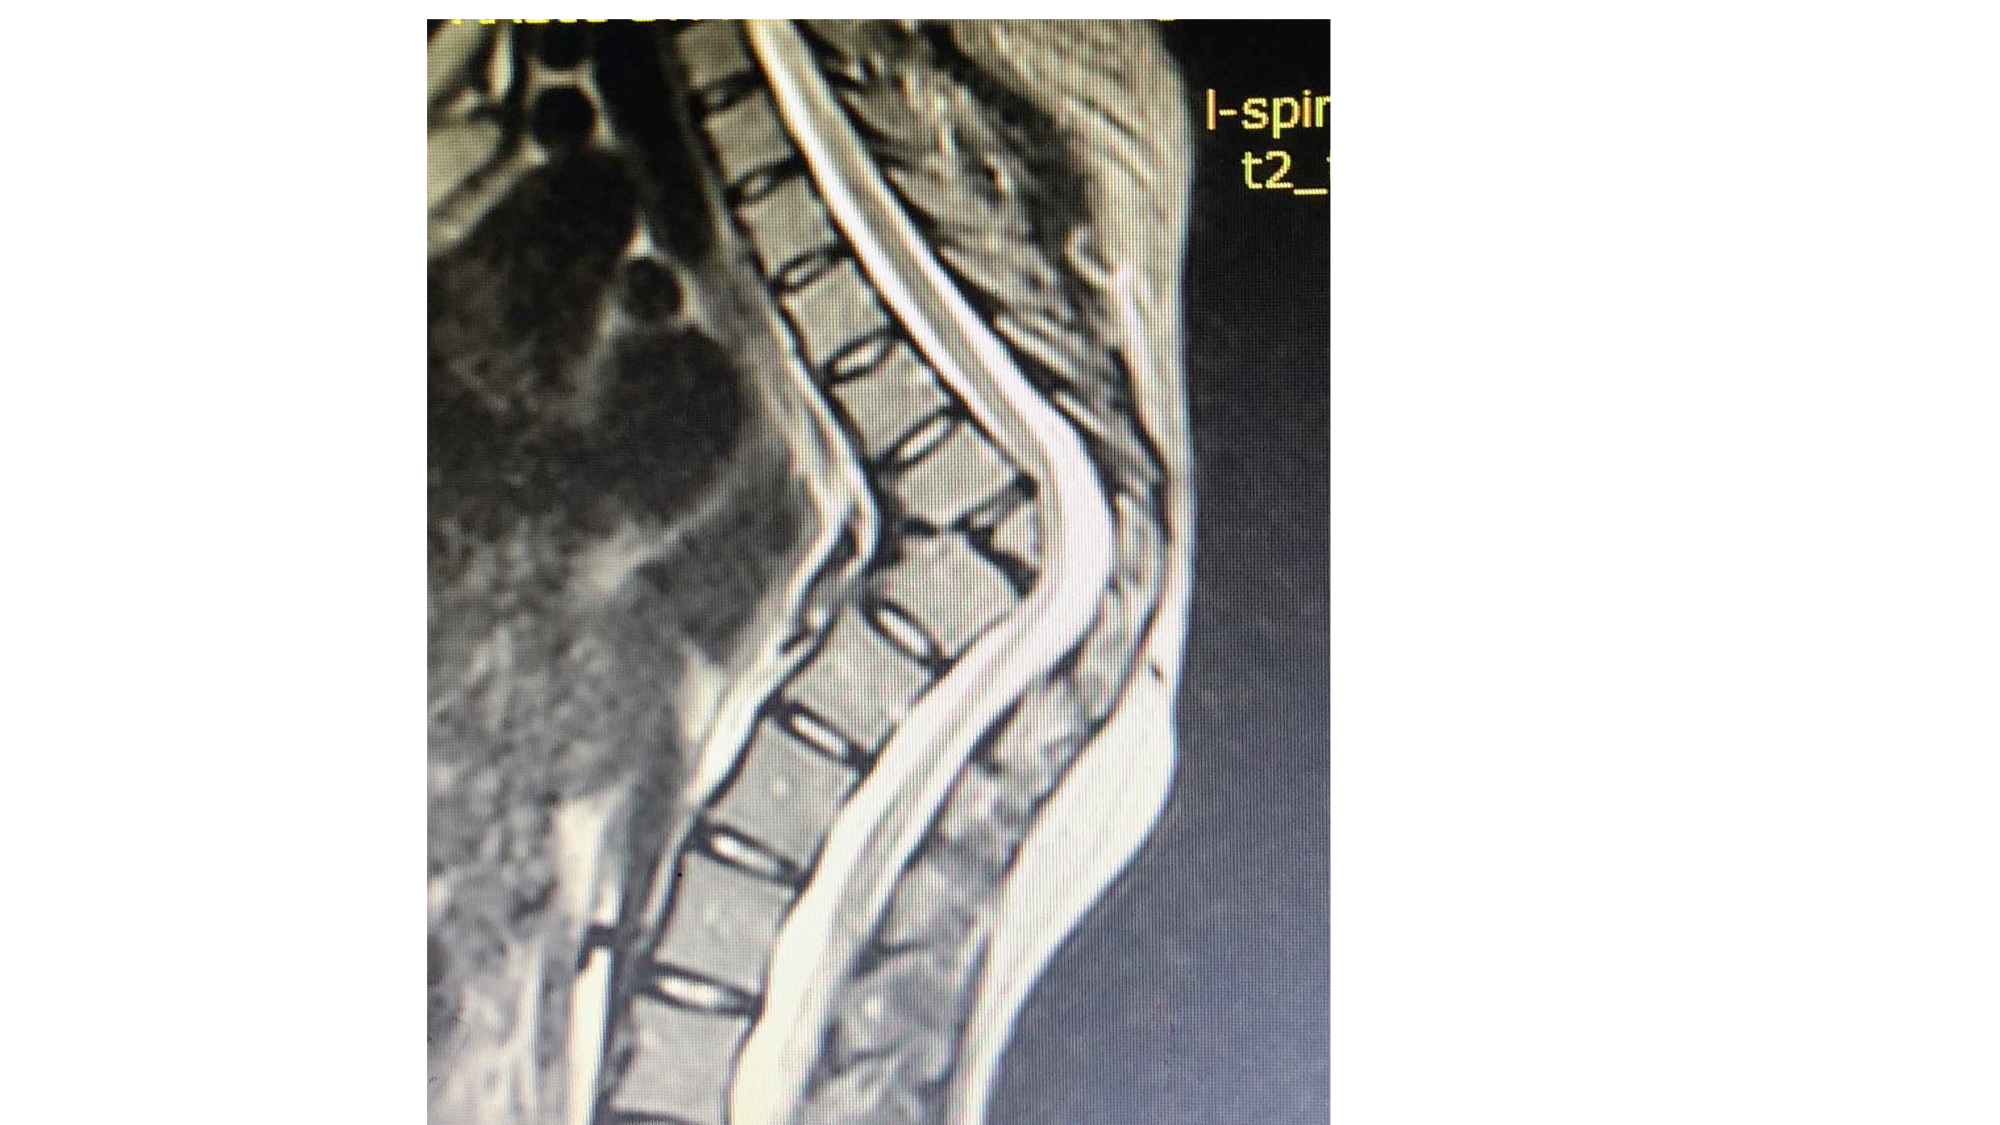

I was also able to meet the first two spine surgery fellows at AaBET. They are both neurosurgeons. The plan after next year is to alternate orthopedic with neurosurgery spine fellows. In addition to their teaching at AaBET, they are mentored by Dr Fasil Mesfin of Univeristy of Missouri, with whom they have weekly cases conferences. They were excited to show me two massive spine tumors they just operated on, one a giant, dumbbell shaped neurofibroma of the lower thoracic spine with bone involvement and preoperative paraparesis; the other a huge aneurysmal bone cyst of posterior lumbar element. Both needed pedicle screw instrumentation and big exposures. I am not a spine surgeon but the operative photos and postop xrays were very impressive.